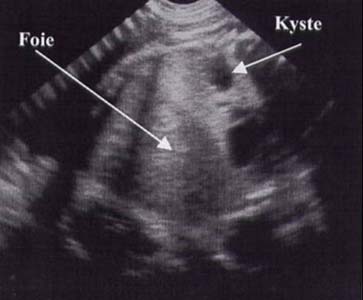

Kyste bronchogénique